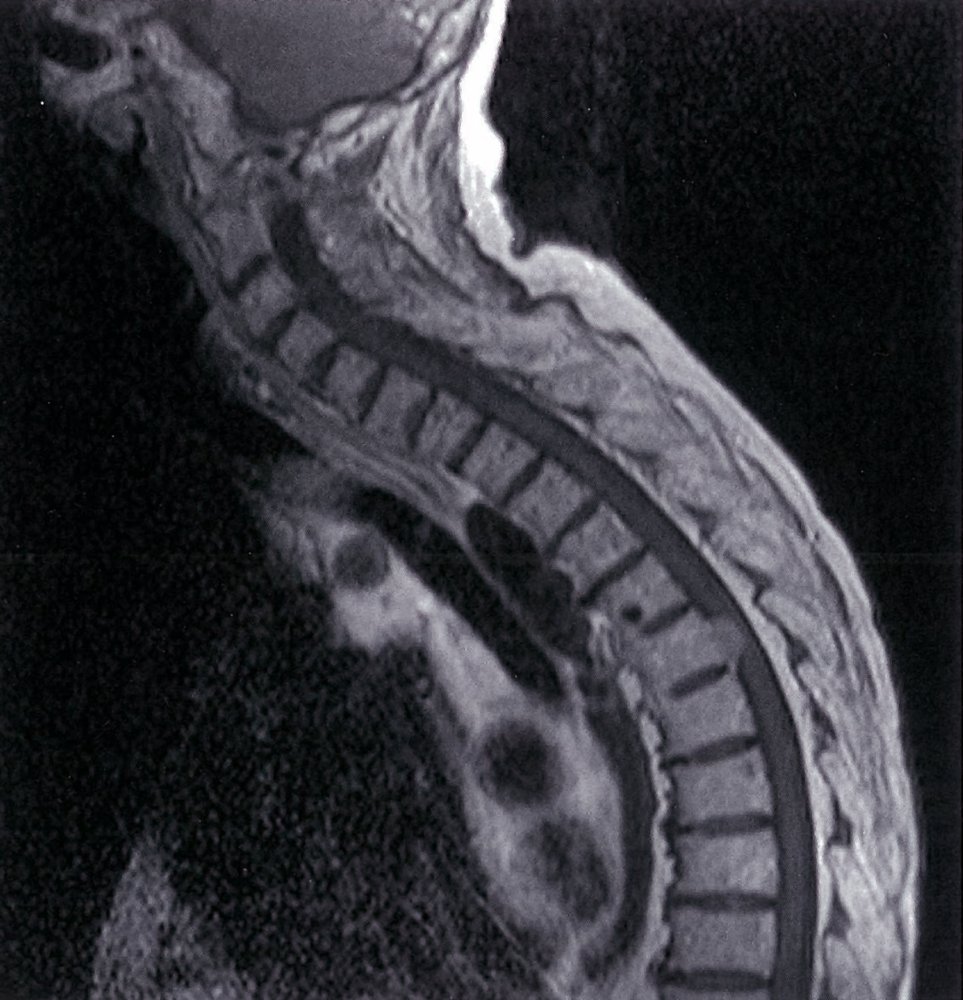

• MRI of the spine (imaging modality of choice) : determines the site of narrowing of the medulla and the underlying pathology

• Myelography (possibly with CT): if MRI is contraindicated (e.g., in patients with metal implants)